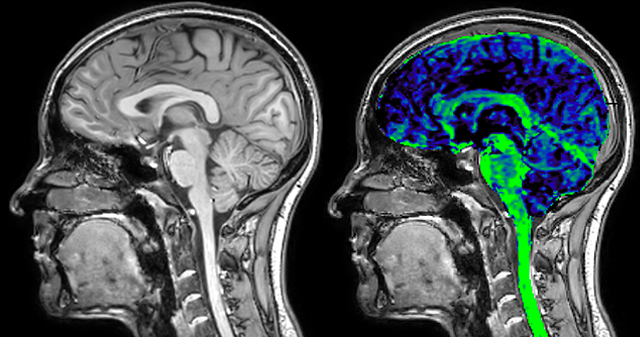

The techniques for measuring myelin have changed a lot over the years. “Since we are using the Elition, our myelin water images are much better. We're now acquiring 1 x 2 x 5 mm voxels and displaying at 1 x 1 x 2.5 mm. For a whole brain we can now measure the fraction of water in the myelin component in only about five or six minutes,” Dr. MacKay says.

of limiting MWI to the brain, even without the cerebellum, we can now spend about the same amount of time and scan the whole brain and the cervical spinal cord, which is a huge boost for us.” Dr. Rauscher says, “For MWI we perform 3D T2 with 32 or more echoes. This used to take a long time, but with Compressed SENSE we can decrease this to ten minutes for the whole head. Because of the large field of view (FOV) on the readout direction, we even get information from the brainstem, which we previously missed when we were using the GRASE approach. Having the whole head scan is nice because it has spatial resolution, orientation and FOV that are comparable to the standard 3D clinical MS scans, including the FLAIR and 3D T2, and a 3D T1 for brain volume.”

T1 - Weighted, Myelin Water Fraction Superimposed

Spinal cord coverage

Smaller, more isotropic voxels

Excellent detail in quantitative maps

Images courtesy of Adam Dvorak, Department of Physics and Astronomy, University of British Columbia